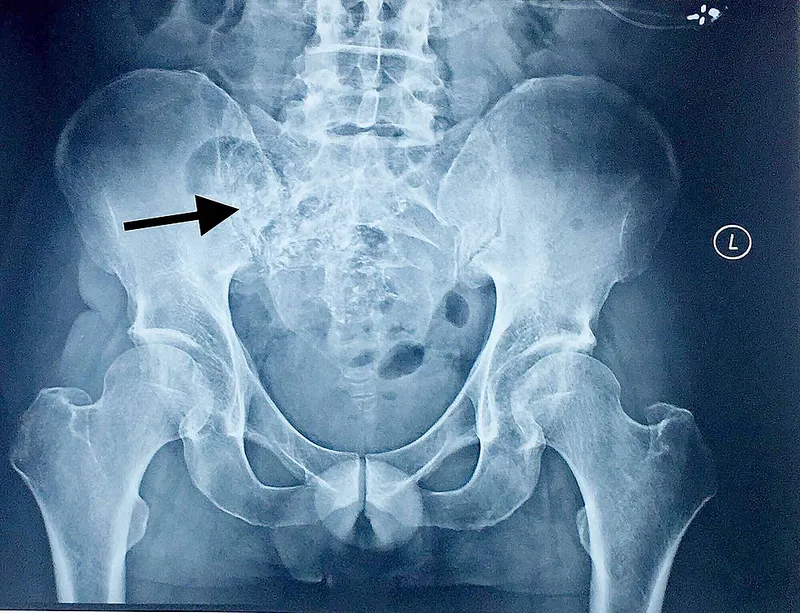

- Brucellar Spondylitis

- Key: Sacroiliitis.

- Signs: 'Pedro Pons' sign' (vertebral erosion), undulant fever.

- Brucellosis often involves the sacroiliac joints and spine (spondylitis).